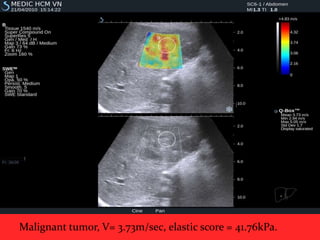

Malignant tumor, V= 3.73m/sec, elastic score = 41.76kPa.

Malignant tumor, V=3.73m/sec, elastic score = 41.76kPa.